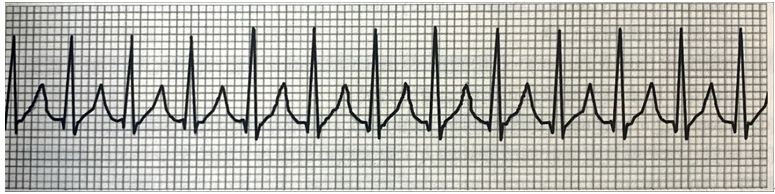

20.下圖心電圖為何種心律? (A)心室頻脈(ventricular tachycardia) (B)心電圖儀遭受干擾 (C)心室纖維顫動(ventricular fibrillation) (D)竇性心率過速(sinus tachycardia)